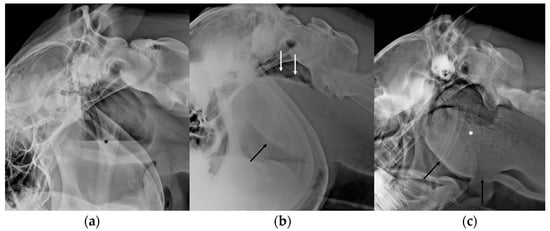

3.5. Masses Involving the Guttural Pouches